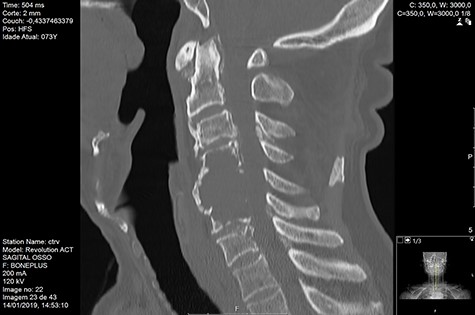

Computed tomography (CT) (Figs 1–3) and magnetic resonance imaging (MRI) (Figs 4–6) of the cervical spine were performed and revealed a lytic lesion involving most of C4, C5 and C6 vertebral bodies with bilateral extension to the posterior spinal elements of C4 and C5 and complete disruption of C4-C5 and C5-C6 intervertebral discs.

The Spinal Instability Neoplastic Score (SINS) [4, 6, 7] for assessing spinal instability from metastatic disease was used and the lesion was deemed unstable (SINS 13), with impending risk of increased neurological damage.

Findings from laboratory tests (serum protein electrophoresis) led to the diagnosis of MM. The patient was placed on a Philadelphia c-spine collar and underwent local 3D external-beam radiotherapy (20Gy in five fractions).